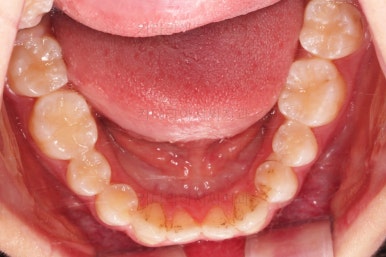

초진 시 입안의 모습입니다.

비밀은 매우 자연스러워 보이지만 아래 앞니 2개가 선천 결손인 상태였습니다.

앞니끼리 맞물리지 않다보니 아래 앞니는 점점 솟구쳐 과개교합(깊게 맞물려 아래 앞니가 거의 보이지 않는 현상)이 되게 됩니다.

아래는 통째로 앞으로 끌고 나오기로 했습니다.

아래턱은 아쉽게도 성장 시킬 수 있는 나이는 지났고, 대신 가능한 선에서 아랫니를 앞으로 빼보기로 했습니다.

아랫니는 중간에 오히려 틈이 생기고 있죠?

아랫니는 이후에 어금니를 앞으로 당겨오면서 빈공간을 줄여 나갑니다.